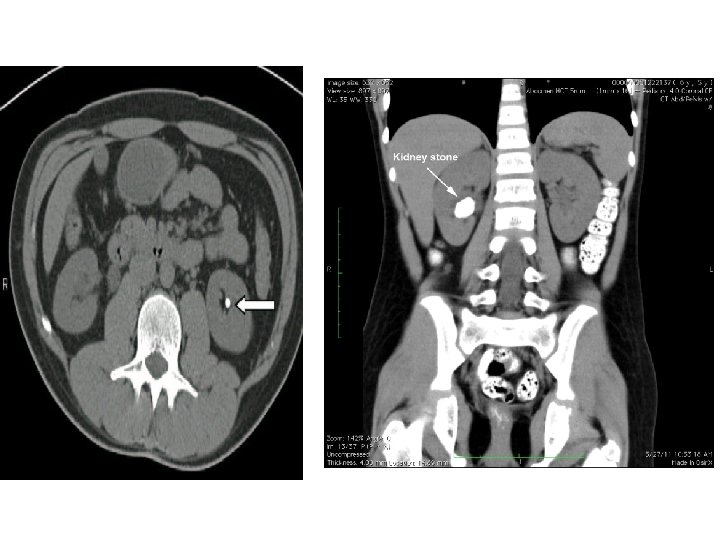

Radyolojik İnceleme • • • Direkt Üriner Sistem Grafisi Ultrasonografi İntravenöz Piyelografi Bilgisayarlı Tomografi Böbrek Sintigrafisi